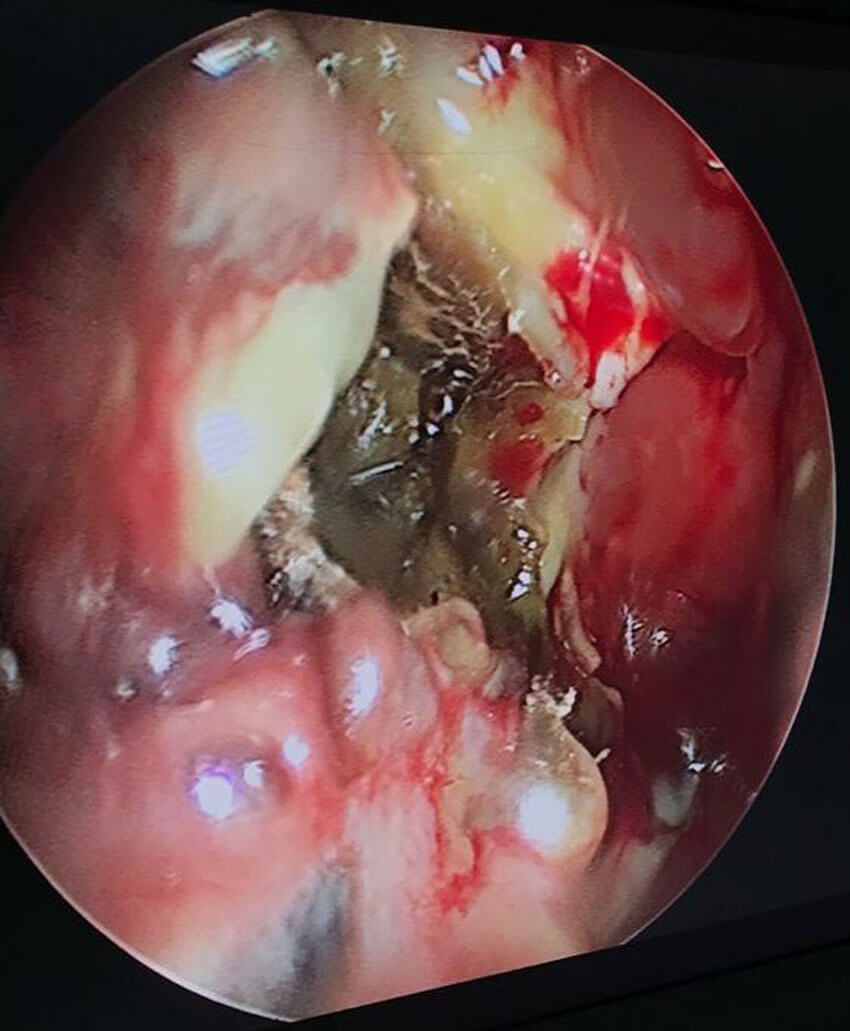

Endoscopic picture of mucor with necrotic tissue in middle meatus.

Cautious use of corticosteroids, strict glycaemic control and a high index of suspicion in considering mucor as a diagnosis are vital. Liberal use of diagnostic nasal (video) endoscopy (DNE) in high-risk groups (post-COVID status, poorly controlled diabetics and extensive use of steroids) is strongly recommended.

In advanced presentations, especially with retro-orbital, retromaxillary disease with loss of vision, irreverent excision of diseased and devitalised tissues with a low threshold for orbital exenteration may have to be considered. In indolent disease, we aim for ‘bleeding healthy (pink) tissue and bone/marrow’ with a reasonable attempt at conservation (anatomical and functional).